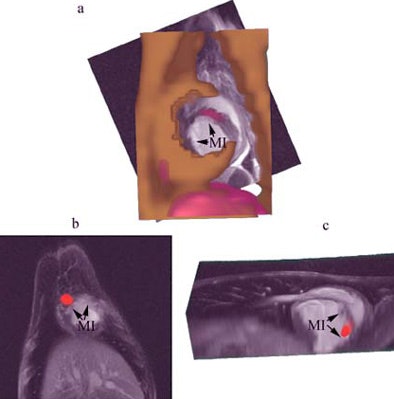

| Combined SPECT/CT and MR images of the heart demonstrating focal uptake of indium-111 oxine-labeled MSCs in the peri-infarcted region. A, CT image (gold) combined with MRI (grayscale) and SPECT (red) shows focal uptake in the myocardial infarct (MI) area. B, focal uptake on SPECT (red) in another animal demonstrating localization of the MSCs to the MI in the two views (B, C). |

The team validated their findings by measuring the radiation levels in these tissues postmortem. MRI images did not reveal the cardiac localization of the stem cells, due to its lower sensitivity.